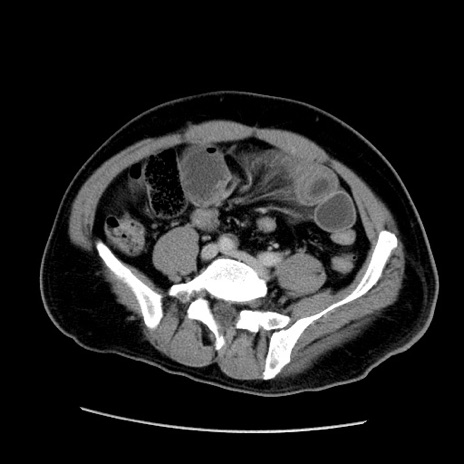

症例

冠状断像